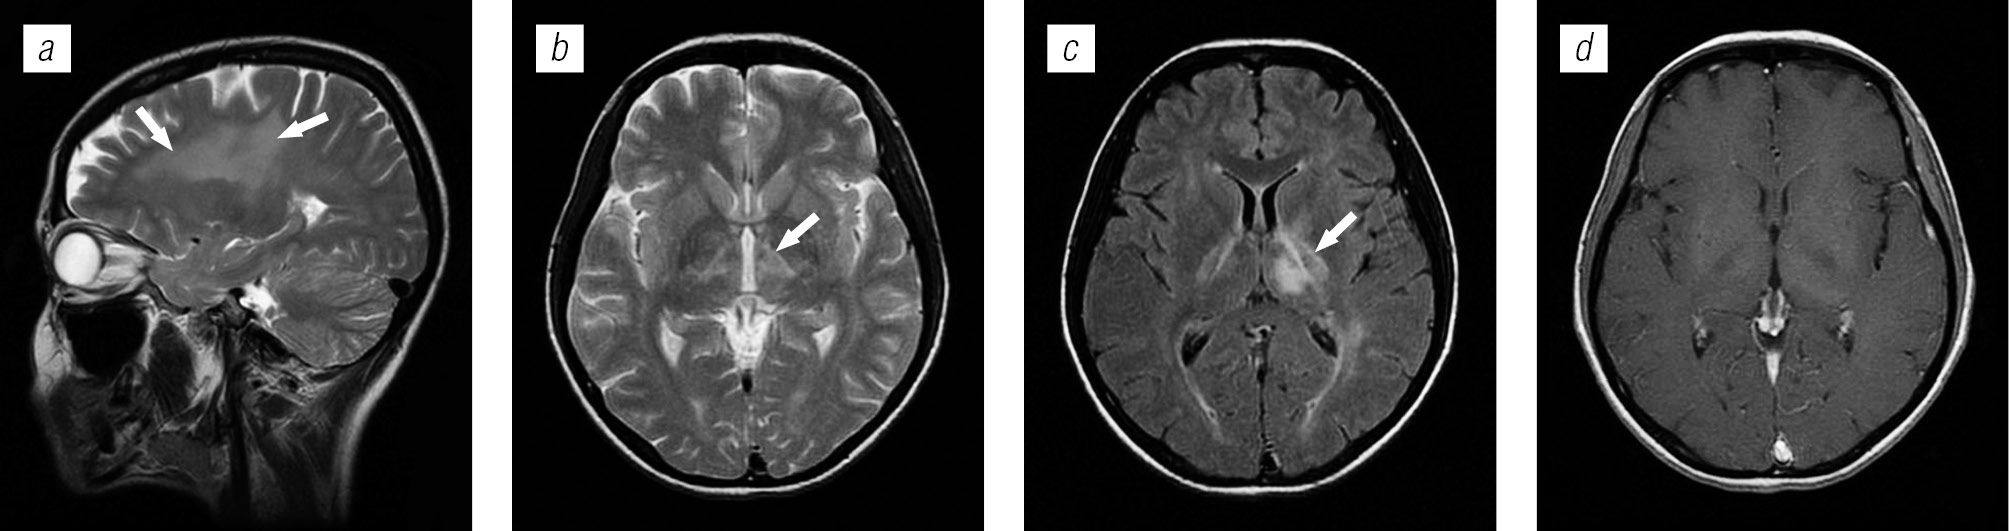

Структура оппортунистических и вторичных заболеваний была представлена токсоплазмозом головного мозга (18,3 %), герпесвирусными поражениями (12,2 %), прогрессирующей мультифокальной лейкоэнцефалопатией (10,24 %), нейроинфекцией неуточненной этиологии (12,2 %), криптококкозом (4,39 %), туберкулезом (2,44 %), лимфомой головного мозга (2,44 %), МАК-инфекцией (0,24 %).

Поражение головного мозга у ВИЧ-инфицированных больных во многом характеризуется синхронностью (микст-инфекция в 8,52 %) и мультифакторностью поражения.